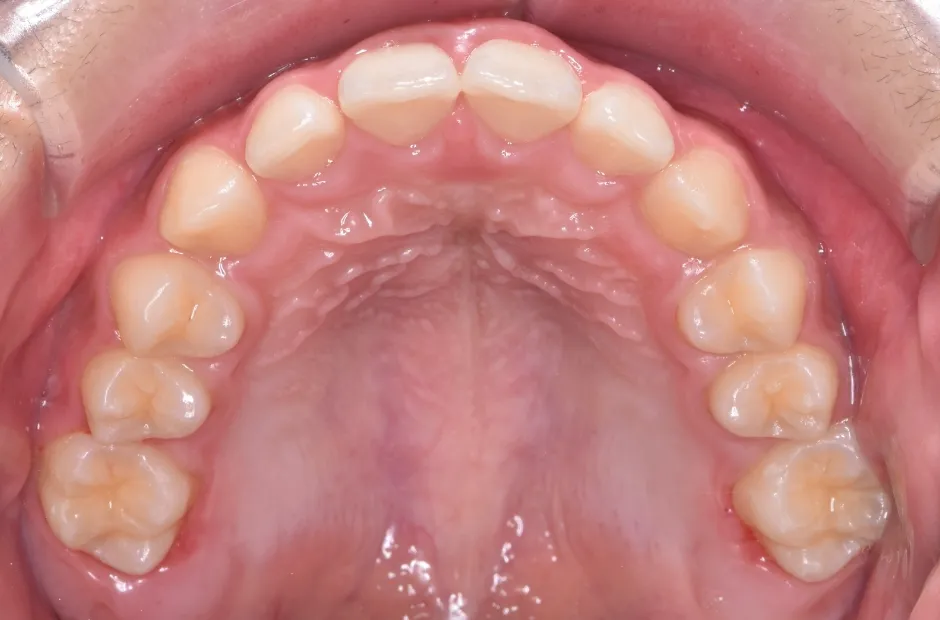

反対咬合

| 診断名・主訴 | 前歯反対咬合 |

|---|---|

| 年齢・性別 | 12歳・男性 |

| 治療期間・回数 | 1年半 18回 |

| 治療に用いた主な装置 | リンガルアーチ(前方誘導弾線) |

| 抜歯部位 | なし |

| 治療費 | 35万円(税抜) |

| リスク・副作用 | 装置による違和感・疼痛・歯肉退縮・歯根吸収・虫歯のリスクなど |